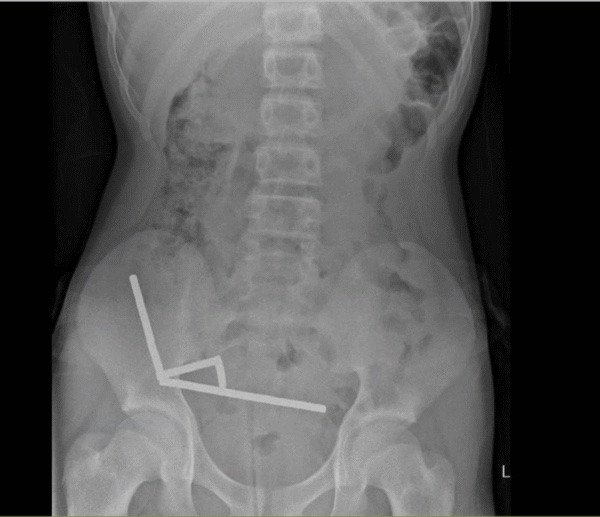

Хлопчик зізнався лікарям, що тиждень тому проковтнув, як він припускав, близько 100 магнітів. Рентгенівський знімок показав, що в його кишечнику утворилися чотири лінійні ланцюги. Ці магніти, з’єднавшись через стінки кишківника, стискали тканини, спричиняючи некроз під тиском (відмирання тканин через брак крові). Незважаючи на складну операцію, підліток одужав і його виписали через вісім днів. Історія підкреслює, наскільки небезпечним може бути проковтування магнітів, навіть якщо це здається невинним жартом чи експериментом.